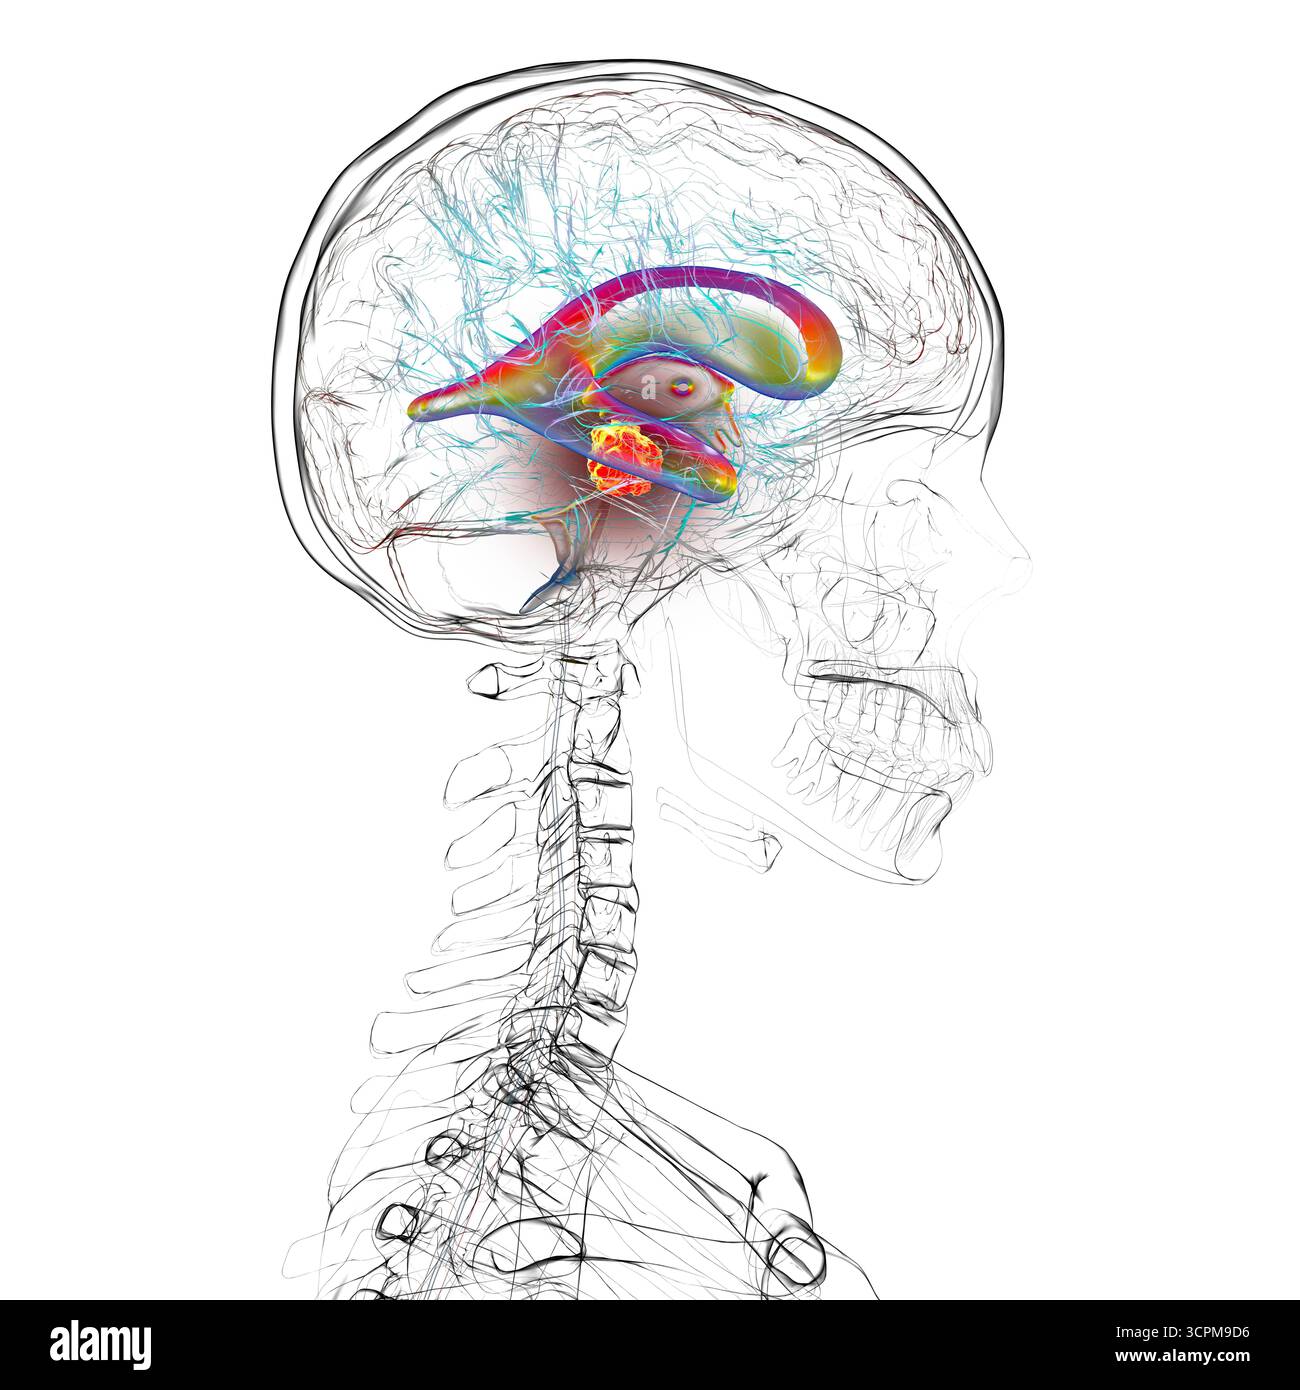

RF3CN8WHW–Darstellung der vergrößerten lateralen und dritten Ventrikel des Gehirns (Hydrozephalus), hervorgerufen durch einen Hirntumor, der den Aquädukt des Gehirns komprimiert.

RF3CN8WHP–Illustration des vergrößerten lateralen und dritten Ventrikels des Gehirns (Hydrozephalus), hervorgerufen durch einen Hirntumor, der den Aquädukt des Gehirns komprimiert.

RF3CPM9D2–Darstellung der vergrößerten lateralen und dritten Ventrikel des Gehirns (Hydrozephalus), hervorgerufen durch einen Hirntumor, der den Aquädukt des Gehirns komprimiert.

RF3CPM9D7–Darstellung der vergrößerten lateralen und dritten Ventrikel des Gehirns (Hydrozephalus), hervorgerufen durch einen Hirntumor, der den Aquädukt des Gehirns komprimiert.

RF3CPM9DA–Darstellung der vergrößerten lateralen und dritten Ventrikel des Gehirns (Hydrozephalus), hervorgerufen durch einen Hirntumor, der den Aquädukt des Gehirns komprimiert.

RF3CPM9D6–Darstellung der vergrößerten lateralen und dritten Ventrikel des Gehirns (Hydrozephalus), hervorgerufen durch einen Hirntumor, der den Aquädukt des Gehirns komprimiert.